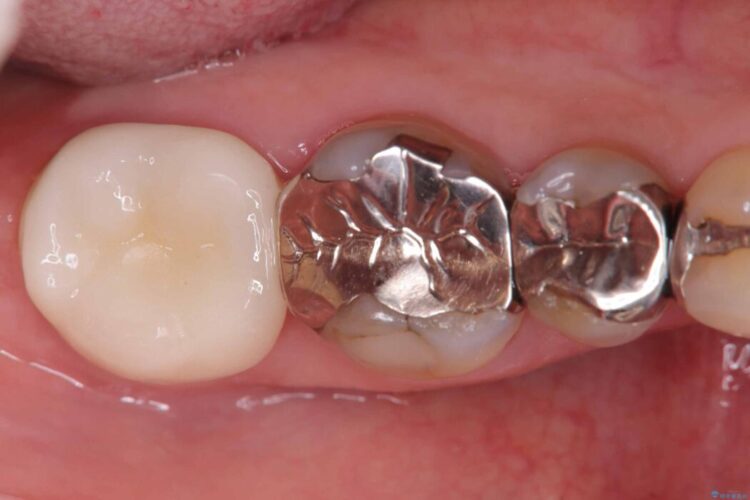

詰め物内部の虫歯治療、隠れた根管の発見

詰め物内部の虫歯治療、隠れた根管の発見 ビフォー 詰め物内部の虫歯治療、隠れた根管の発見 アフター

奥歯の詰め物が取れたとご来院された患者様です。